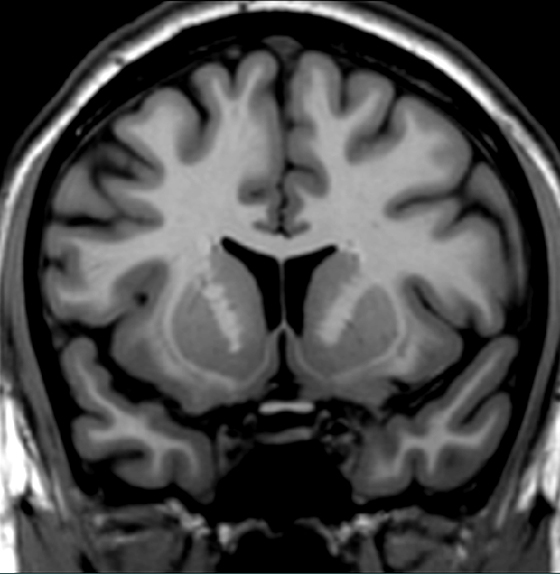

Is this scan rostral or caudal to the anterior commissure?

A. Rostral

B. Caudal